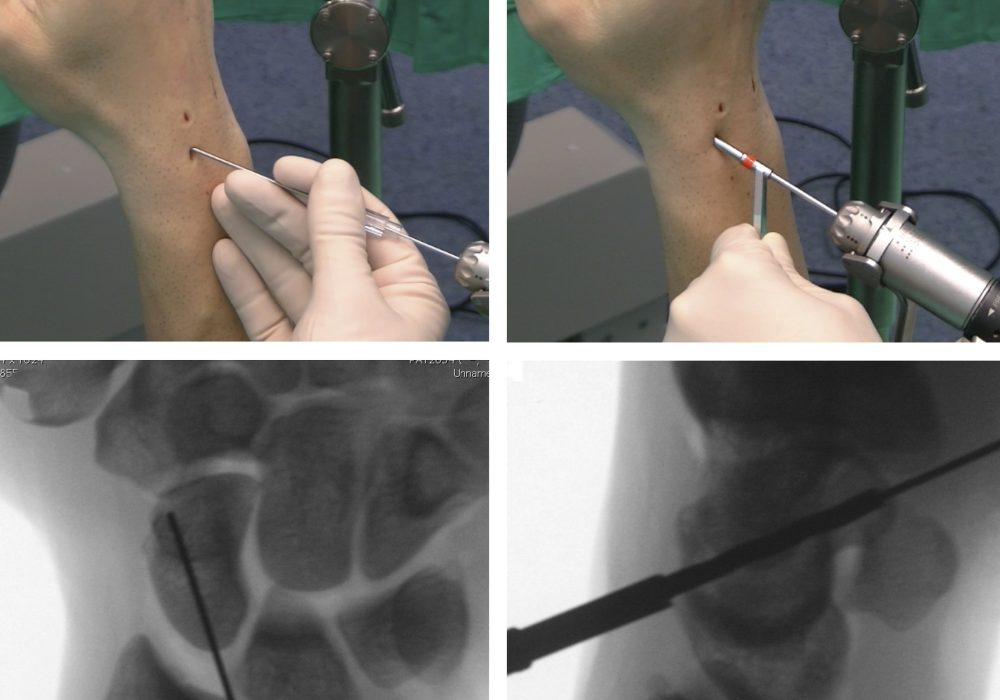

- Arthroscopic-Assisted Reconstruction: Minimally invasive approach to reduce morbidity.

Procedure Overview

- The wrist is exposed through a dorsal incision.

- The scapholunate interval is assessed and debrided.

- The chosen graft is harvested and prepared.

- The graft is fixed between the scaphoid and lunate bones using screws, anchors, or sutures.

- Temporary pinning may be used to maintain alignment during healing.

- The wrist is immobilized postoperatively.